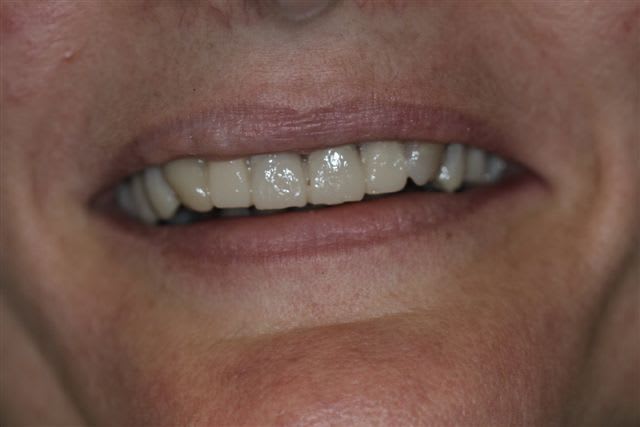

comme je l'ai dis plus haut le wax up ne parle pas à la patiente, j'ai donc au cours d'un rdv long, et à partir d'une empreinte du waxup, fait un "provisoire de présentation" en résine, sans fioriture juste pour que la dame comprenne mieux ce que je pouvais essayer de lui apporter.

On peut faire un montage sur photoshop mais ça n'a pas le même impact.

La patiente m'a demandé une fois le "maquillage" en place l'autorisation de le montrer à son mari...retour deux heures après, pas contente du tout ...que je dépose la résine.

et:" mon mari est d'accord pour refaire le haut mais le bas je ne peux pas"!

Et bien pas de bras pas de chocolat madame, pas de bas pas de haut...à plus tard.